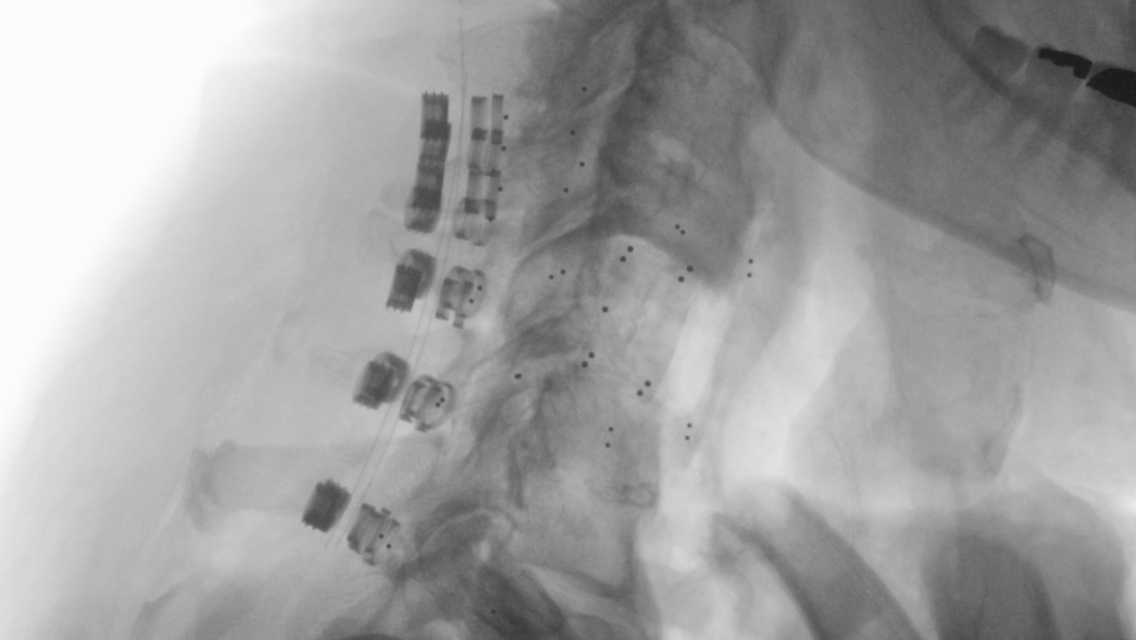

The CMORE® Cervicothoracic (CT) System is an enhanced set of instruments and implants for posterior stabilization of the cervicothoracic spine. The world’s first spinal implants made of nonmetallic and radiolucent BlackArmor® technology now enable a full spectrum of treatment modalities in adjuvant tumor therapy and enhance postoperative imaging diagnostics in the cervicothoracic spine.

Consisting of a full portfolio of polyaxial screws, straight and precontoured rods, axial and parallel connectors, the CMORE® CT System provides the versatility needed to accommodate variations in patients’ anatomy and pathology.

- Transition between CMORE® CT and VADER® Pedicle System by a variety of BlackArmor® Carbon/PEEK connectors